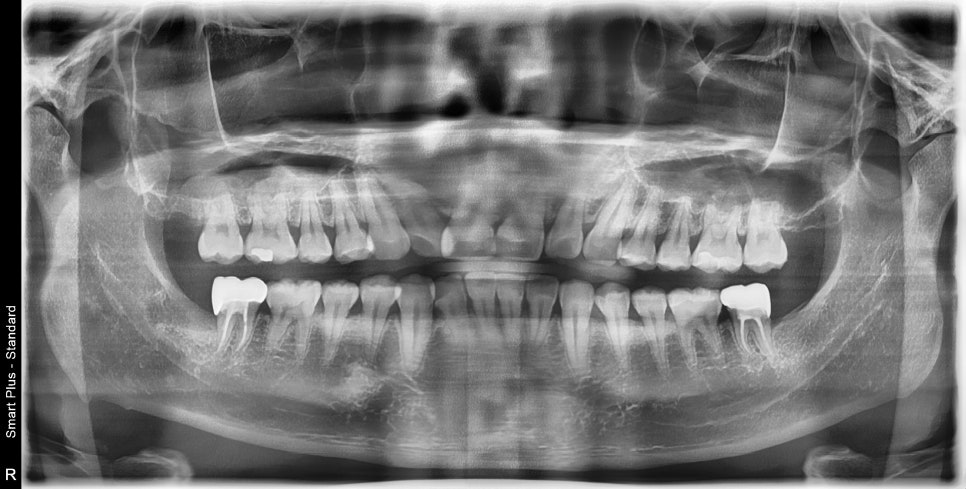

매복 사랑니 발치에 의해 생기는 충치는 잇몸 하방 깊은 곳에서 생기기 쉽습니다.

보철물 경계 부분이 너무 깊은 위치에 생길 수밖에 없어서 준비과정이 쉽지 않았지만

환자분께서도 잘 도와주셔서 사랑니 발치, 신경치료, 보철치료까지 만족스러운 결과가 나올 수 있었습니다^^